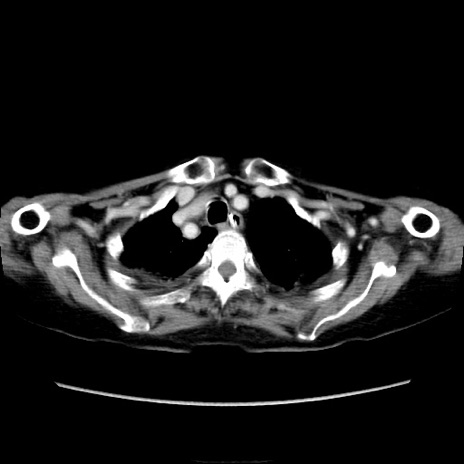

症例40(横断像)

【症例】90歳代女性

【主訴】腹痛・嘔吐

【現病歴】 食欲低下、嘔吐があり昨日他院受診。肺炎と診断され入院となる。入院後より腹部全体に圧痛あり。胃管留置され経過みていたが、症状持続するため、

当院転院となる。

【既往歴】胸椎圧迫骨折、胆石症

【身体所見】腹部:中央に激痛あり、圧痛あり、反跳痛不明

【データ】WBC 17100、CRP 18.82